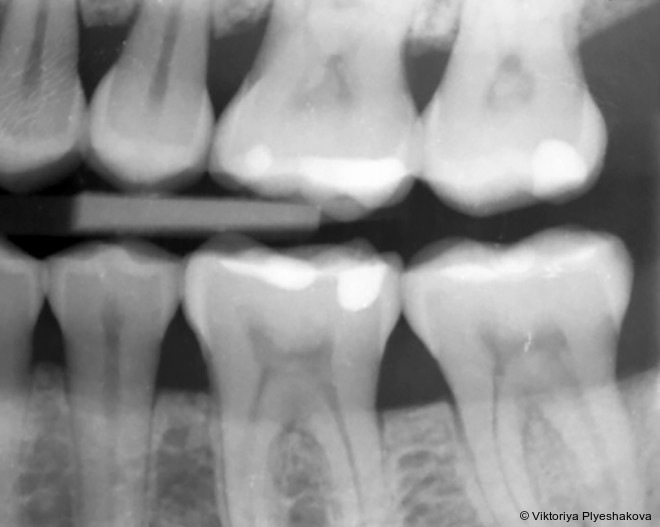

Ausgeprägter Knochenverlust in Molarenregionen

Periapikale Röntgenaufnahmen zeigten einen vertikalen/angulären Knochenverlust in den Regio­nen 16, 17, 36-37 und 46-47, der sich bis zum mittleren Drit­tel der Wurzeln erstreckte. Gemäß der Klassifikation der Parodontalerkrankungen von 2017 wurde eine lokalisierte Parodontitis – Sta­dium III (schwer), Grad C (schnelle Progression) diagnostiziert. Die Erkrankung war auf die Mola­renregionen mit Resttaschen > 6 mm begrenzt.